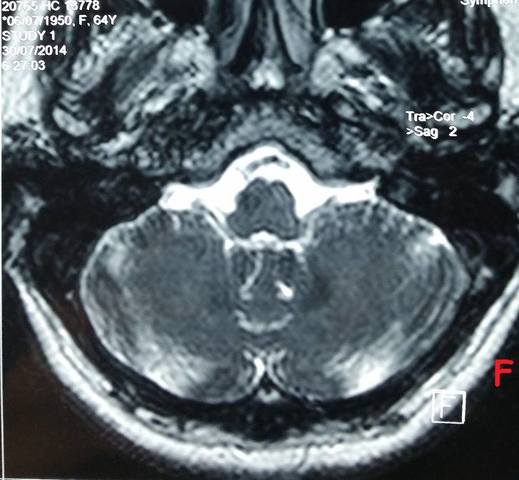

Se publicó el primer libro sobre ECJ con 150 casos. Ya para entonces estaba clara la imagen histopatológica: cambio espongiforme, ausencia del infiltrado inflamatorio, pérdida neuronal, y placas amiloides.

Griffith y Latarget propusieron que las EET podrían tratarse de errores en el procesamiento de las proteínas ocasionando el depósito de péptidos anormales dada la ya conocida carencia de ADN y ARN su largo periodo de incubación, la ausencia de respuesta inmunológica y de infiltrado inflamatorio de estructuras visibles al microscopio electrónico, su extrema resistencia a la radiación ultravioleta, los rayos X, al formaldehido y al mismo tiempo, su sensibilidad a los métodos que degradan proteínas